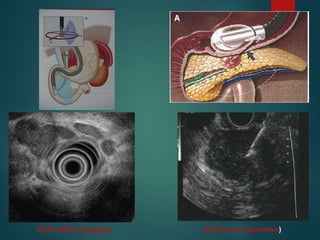

Strumento radiale

Strumento lineare

EUS radiale (imaging) EUS lineare (operativa)

EUS radiale (imaging)EUS lineare (operativa)